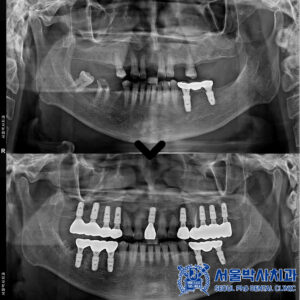

신흥동치과, 음식 씹을 때 아파요 (재신경치료 및 임플란트로 치료)

신흥동치과, 음식 씹을 때 아파요 (재신경치료 및 임플란트로 치료) 안녕하세요. 신흥동치과 서울박사치과입니다. 치아 신경치료는 치아를 살리기 위한 마지막 수단으로 불릴 만큼 중요한 치료인데요. 특히 재신경치료의 경우 처음 신경치료가 제대로 되지 않았거나 이후 문제가 생겼을 때 다시 진행하는 치료로, 일반적인 신경치료에 비해 난이도가 높고 의료진의 섬세한 손기술과 경험이 요구됩니다. 오늘은 더보기…